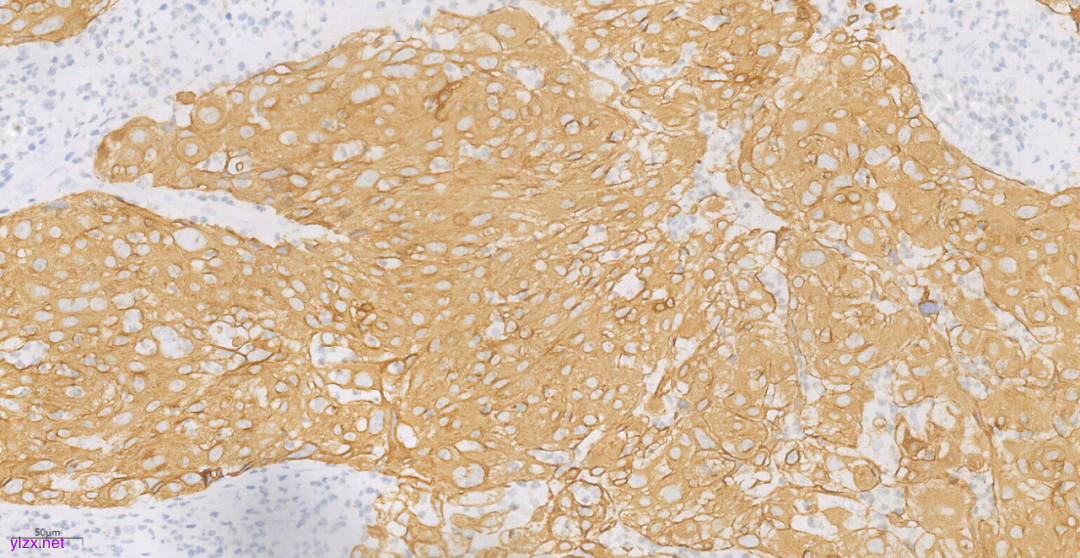

3.3免疫组化(图10-图12):

鳞癌成分CK(+),P40(+),CK5/6(+),p63(+),CK7(-),CK20(-),ER(-),PR(-),WT-1(-),Ki-67(约70%+).

图11 免疫组化示肿瘤细胞CK5/6(+)。

免疫表型:SCC肿瘤细胞CK5/6、p63、p40阳性,ER、PR阴性。